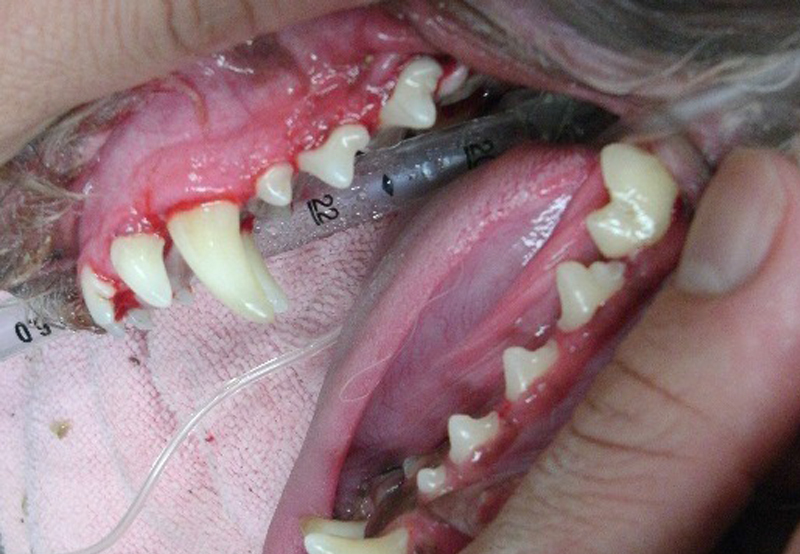

歯科

重度に歯石がついてしまった場合には、クリーニングする必要があります。

治療後は口臭が減り、ごはんの食べ方もよくなります。